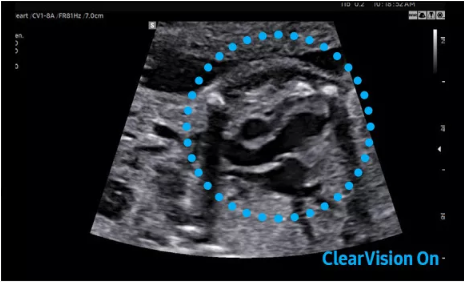

2D成像方面,Hera i10集成了包括ShadowHDR?、HQ-Vision?、ClearVision等多項具有三星“血統(tǒng)”的技術(shù),加強了圖像的陰影抑制、減少偽影、緩和模糊區(qū)。